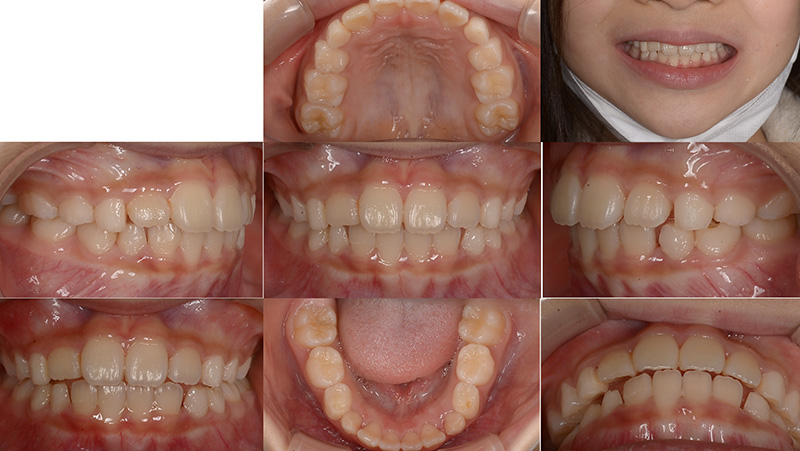

Case01インビザライン・ファーストによる矯正治療例

お子さんの前歯のガタガタが気になると来院されました。今の歯並びも気になるが、大人の歯に生え変わった後も綺麗な状態にしてあげたいという保護者のご希望があり、小児矯正から生え変わったあとの矯正までをしっかりとサポートする「通期矯正」を行いました。

ファイナル 2022.2.12

| 主訴 | 上下顎前歯のガタガタ |

|---|---|

| 診断 | ターミナルプレイン バーティカル 上下顎前歯叢生 |

| 矯正方法 | インビザラインファーストによるマウスピース矯正 |

| 矯正期間 | 6か月・8回 |

| 費用 | 490,000円(税別) |

| 調整料 | 月1回 5,000円(税別) |